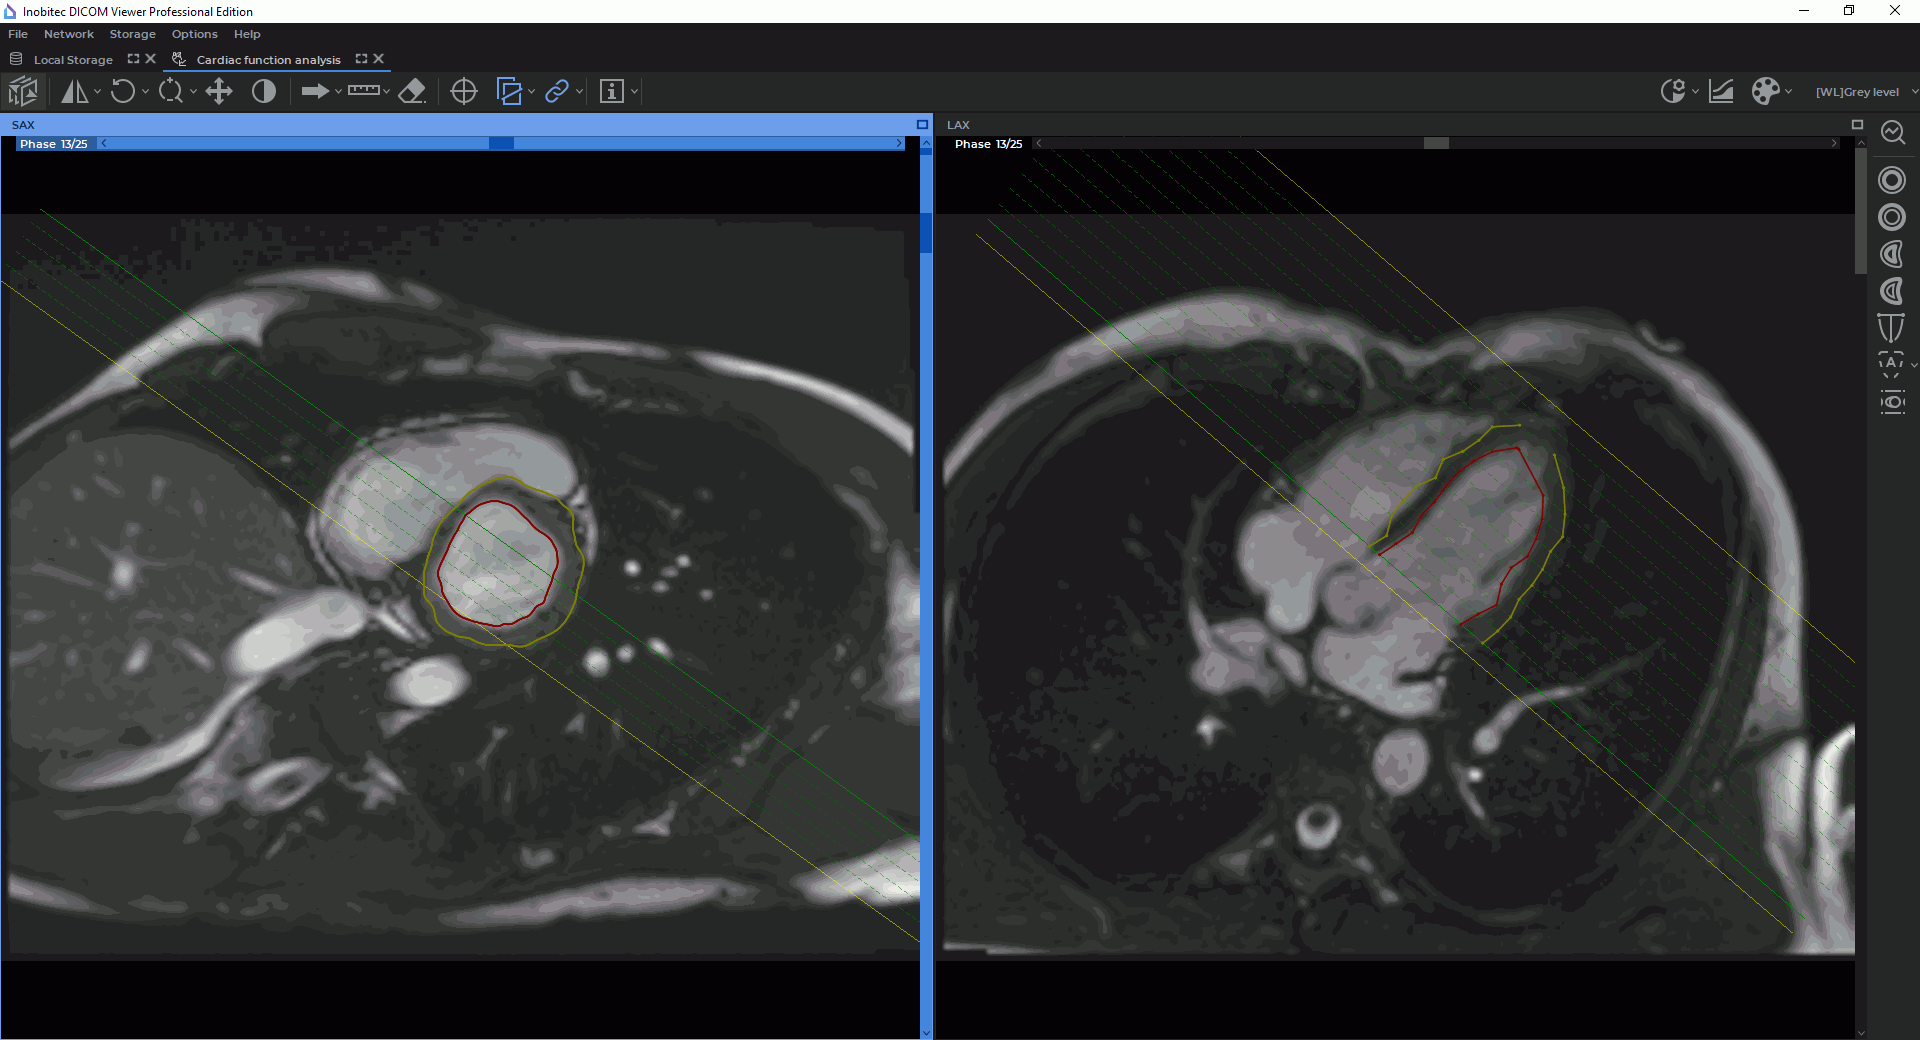

In the Cardiac analysis tab, you can see two windows, with the SAX merged series and the LAX merged series (Fig. 8.2). The toolbar for cardiac function analysis is on the right-hand side of the tab.

Under the SAX and LAX windows, you can see the contours panel aimed for navigation between images and contour management (for details see Section 8.1.7). By default, the panel is expanded.

By default, all the slices for the current phase are shown in the SAX window. The phases may be switched by moving the slider along the horizontal scroll bar at the top of the SAX window or on the contour panel.

| The Endocardial LV contour button is aimed for building and editing the inner contour of the left ventricle manually (the contour is shown in red) |

| The Epicardial LV contour button is aimed for building and editing the outer contour of the left ventricle manually (the contour is shown in yellow) |

The functional parameters of the left and the right ventricles are calculated on the basis of the contours built. Contours can be built separately for each slice and phase in the window with the SAX merged series. The contour boundaries are shown as points on the slices in the window with the merge LAX series. If two or more contours were built for one phase, the points can be connected by segments. You cannot build contours in the window with a LAX merged series.

Automatic contouring of the left ventricle endocardium and epicardium are performed in the window with the SAX merged series for all the phases with the left ventricle extension and all the slices within the extension. The contour boundaries are shown on the slices in the window with the LAX merged series (Fig. 8.6).

Automatic contouring of the left ventricle endocardium and epicardium is performed in the window with the SAX merged series for all the phases. The contour boundaries are shown on the slices in the window with the LAX merged series (Fig. 8.6).